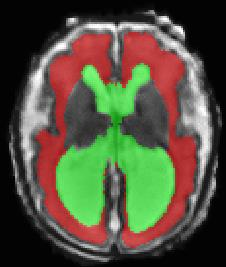

Limiting failures of machine learning systems is of paramount importance for safety-critical applications. In order to improve the robustness of machine learning systems, Distributionally Robust Optimization (DRO) has been proposed as a generalization of Empirical Risk Minimization (ERM). However, its use in deep learning has been severely restricted due to the relative inefficiency of the optimizers available for DRO in comparison to the wide-spread variants of Stochastic Gradient Descent (SGD) optimizers for ERM. We propose SGD with hardness weighted sampling, a principled and efficient optimization method for DRO in machine learning that is particularly suited in the context of deep learning. Similar to a hard example mining strategy in practice, the proposed algorithm is straightforward to implement and computationally as efficient as SGD-based optimizers used for deep learning, requiring minimal overhead computation. In contrast to typical ad hoc hard mining approaches, we prove the convergence of our DRO algorithm for over-parameterized deep learning networks with ReLU activation and a finite number of layers and parameters. Our experiments on fetal brain 3D MRI segmentation and brain tumor segmentation in MRI demonstrate the feasibility and the usefulness of our approach. Using our hardness weighted sampling for training a state-of-the-art deep learning pipeline leads to improved robustness to anatomical variabilities in automatic fetal brain 3D MRI segmentation using deep learning and to improved robustness to the image protocol variations in brain tumor segmentation. Our code is available at https://github.com/LucasFidon/HardnessWeightedSampler.